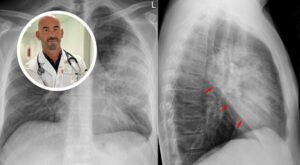

Fare una visita dal medico, una radiografia del torace o una TAC per vedere che non ci siano, appunto, dei segni di polmonite e poi, naturalmente, fare un’adeguata diagnostica, cioè fare il tampone per vedere se è un virus, per vedere se è un batterio e a quel punto poi di gestire come come curarlo.